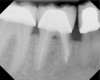

Fig 19. Preoperative radiograph of a case demonstrating apical periodontitis. Courtesy of Dr. Allen Ali Nasseh.

Figure 19

Fig 20. Immediate postoperative radiograph. Courtesy of Dr. Allen Ali Nasseh.

Figure 20

Fig 21. 5-year follow-up with complete healing. Courtesy of Dr. Allen Ali Nasseh.

Figure 21